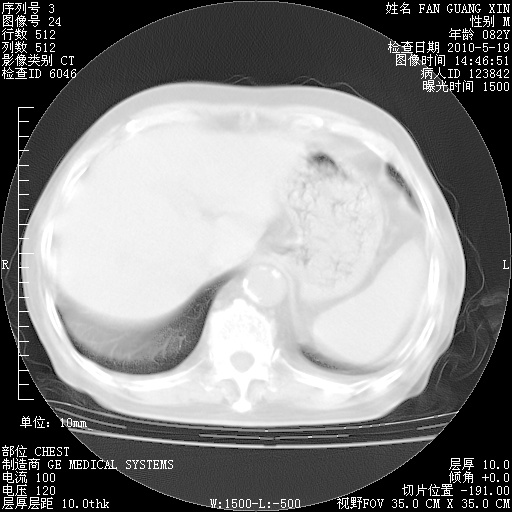

复查肺部CT,明显好转。为什么发热呢?

治疗3周后的肺部CT